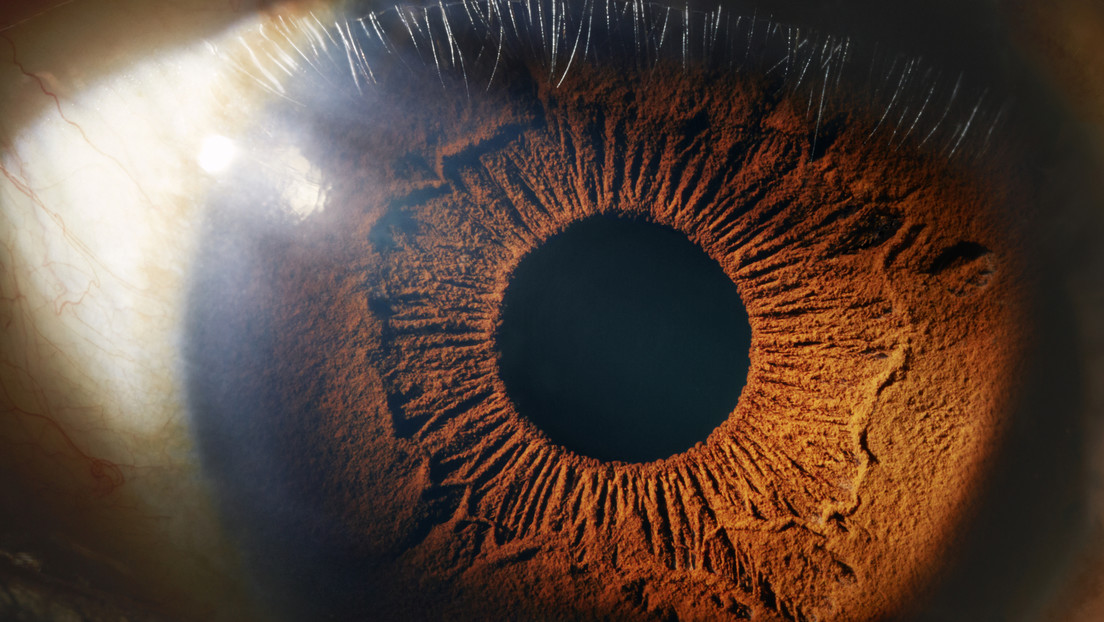

El cuerpo humano cambia silenciosamente con el tiempo. Entre esas transformaciones inevitables aparece la presbicia, una condición...

Ante las limitaciones de las pruebas tradicionales para detectar la osteoporosis, investigadores desarrollaron RetiAGE, un sistema de...